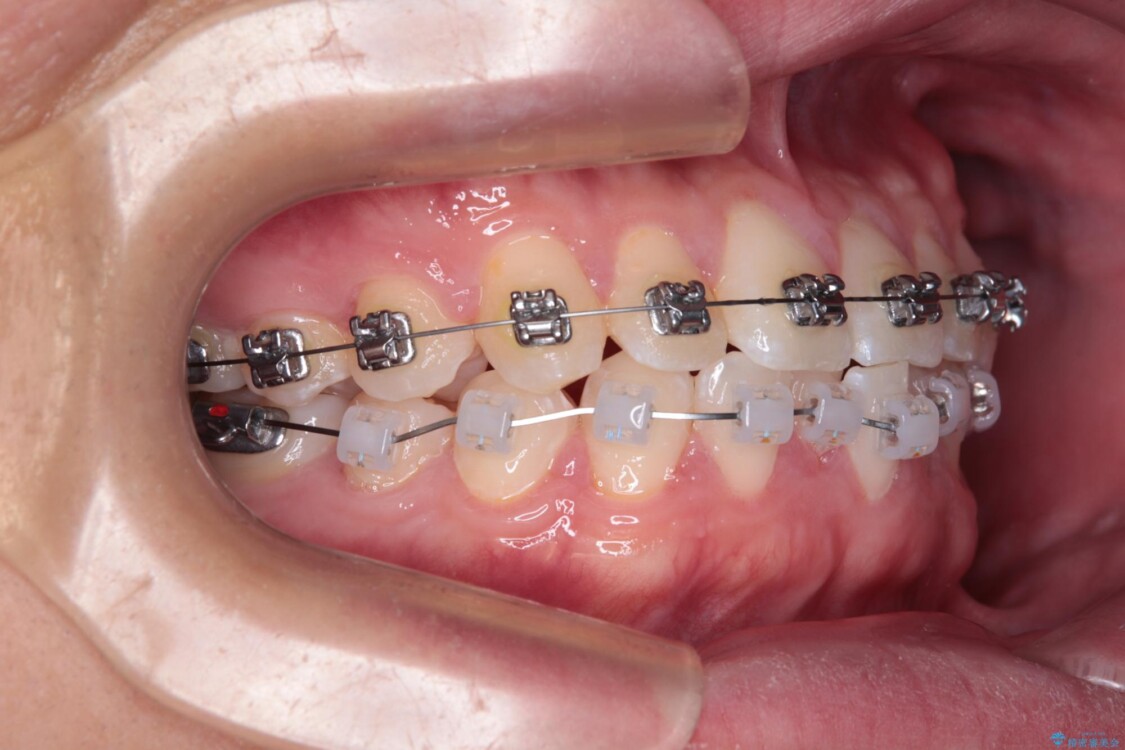

治療途中

• 前歯のガタガタ・奥歯のかみ合わせ(シザーズバイト)を改善|1年半で完了したメタルブラケット矯正 治療途中画像

・奥歯のシザーズバイト改善には、口蓋側にアンカースクリュー(TAD)を設置し、矯正用ゴムで内側に牽引

・捻転した第二小臼歯は、ワイヤーと矯正用ゴムの力を用いて正しい位置へ回転移動